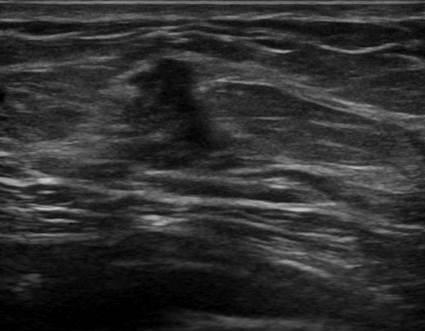

Ung thư tuyến vú

» Thông tin: Nữ giới – 45 tuổi.

» Lâm sàng: Kiểm tra sức khỏe.